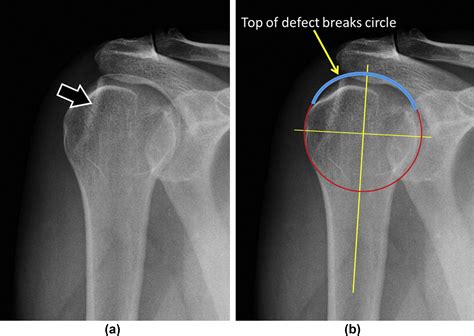

• Imaging studies: X-rays, MRI, or CT scans may be used to visualize the shoulder joint and confirm the presence of a Hill Sachs Lesion. These imaging studies can also help determine the size and location of the lesion, which is important for treatment planning.